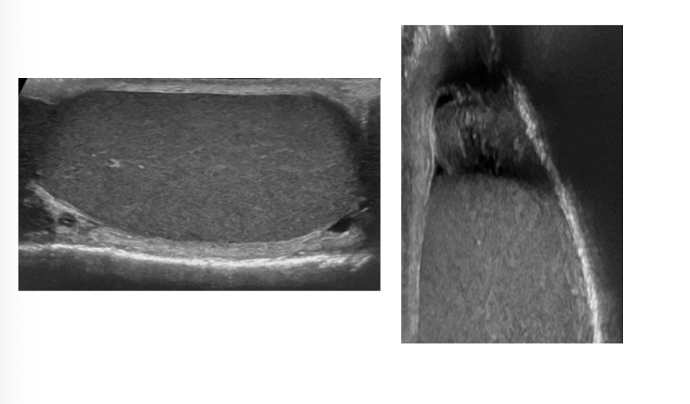

What is this?

Normal right testicle and epidimymis